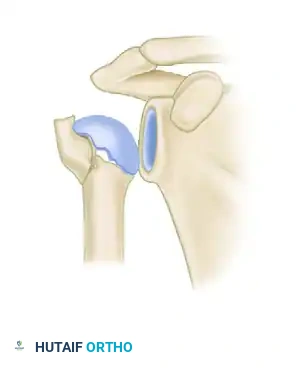

| كسر الأربعة أجزاء | تنفصل جميع الأجزاء الأربعة عن بعضها. يكون رأس العظمة هنا معزولاً ومحروماً من التروية الدموية، مما يرفع خطر نخر العظام بشكل كبير. |

إليك بعض الصور الإشعاعية والرسوم التوضيحية الإضافية التي توضح أشكال التثبيت الجراحي المختلفة لكسور أعلى عظمة العضد